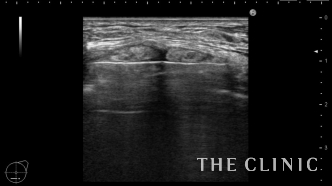

ベイザーリポで壊死した脂肪を崩して吸引します。

吸引後です。